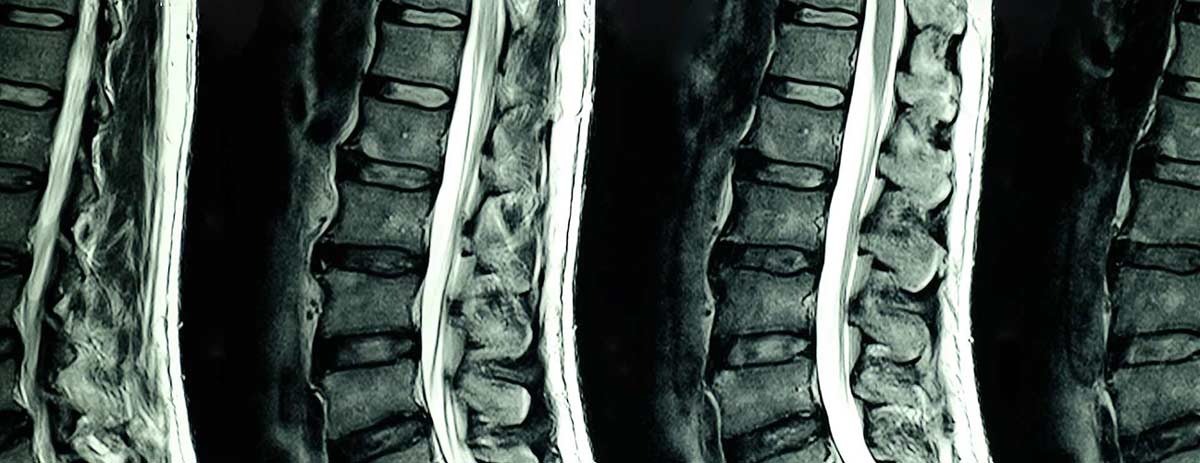

The Coronavirus disease (COVID-19) pandemic outbreak by unprecedented strain by spread of Severe Acute Respiratory Syndrome Coronavirus 2 (SARS-CoV-2) virus has entirely changed Spinal Imaging market dynamics worldwide. Spinal Imaging practices have been drastically impacted irrespective of specialties as all healthcare providers are trying to triage the only urgency of daily imaging procedures and to find new ways and methods for management of less urgent imaging procedure where possible, which has drastically changed in the demand of Spinal Imaging devices and equipment.

FIGURE 1 DBMR INSIGHTS ON COVID-19 PANDEMIC IMPACT ON GLOBAL SPINAL IMAGING MARKET DYNAMICS